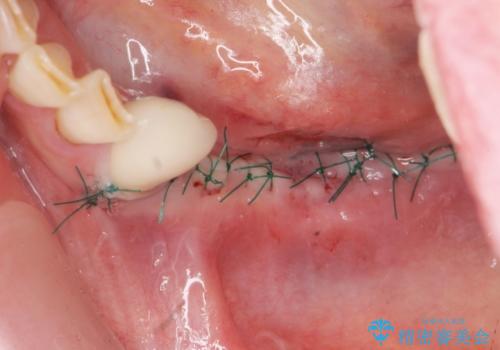

入れ歯を外し、またしっかりと噛んで食事を楽しめるようになるためにインプラントによる治療を計画します。

- 91万円(ストローマンインプラント×2・骨造成・チタンカスタムアバットメント×2・フルジルコニアクラウン×3)費用は治療当時の料金となります

- 外科手術のため、術後に痛みや腫れ、違和感を伴います